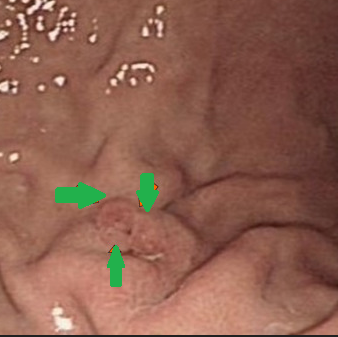

Gastroscopy. Green arrows: orifice of the gastrocolic fistula (Courtesy Dr. V. Penopoulos)